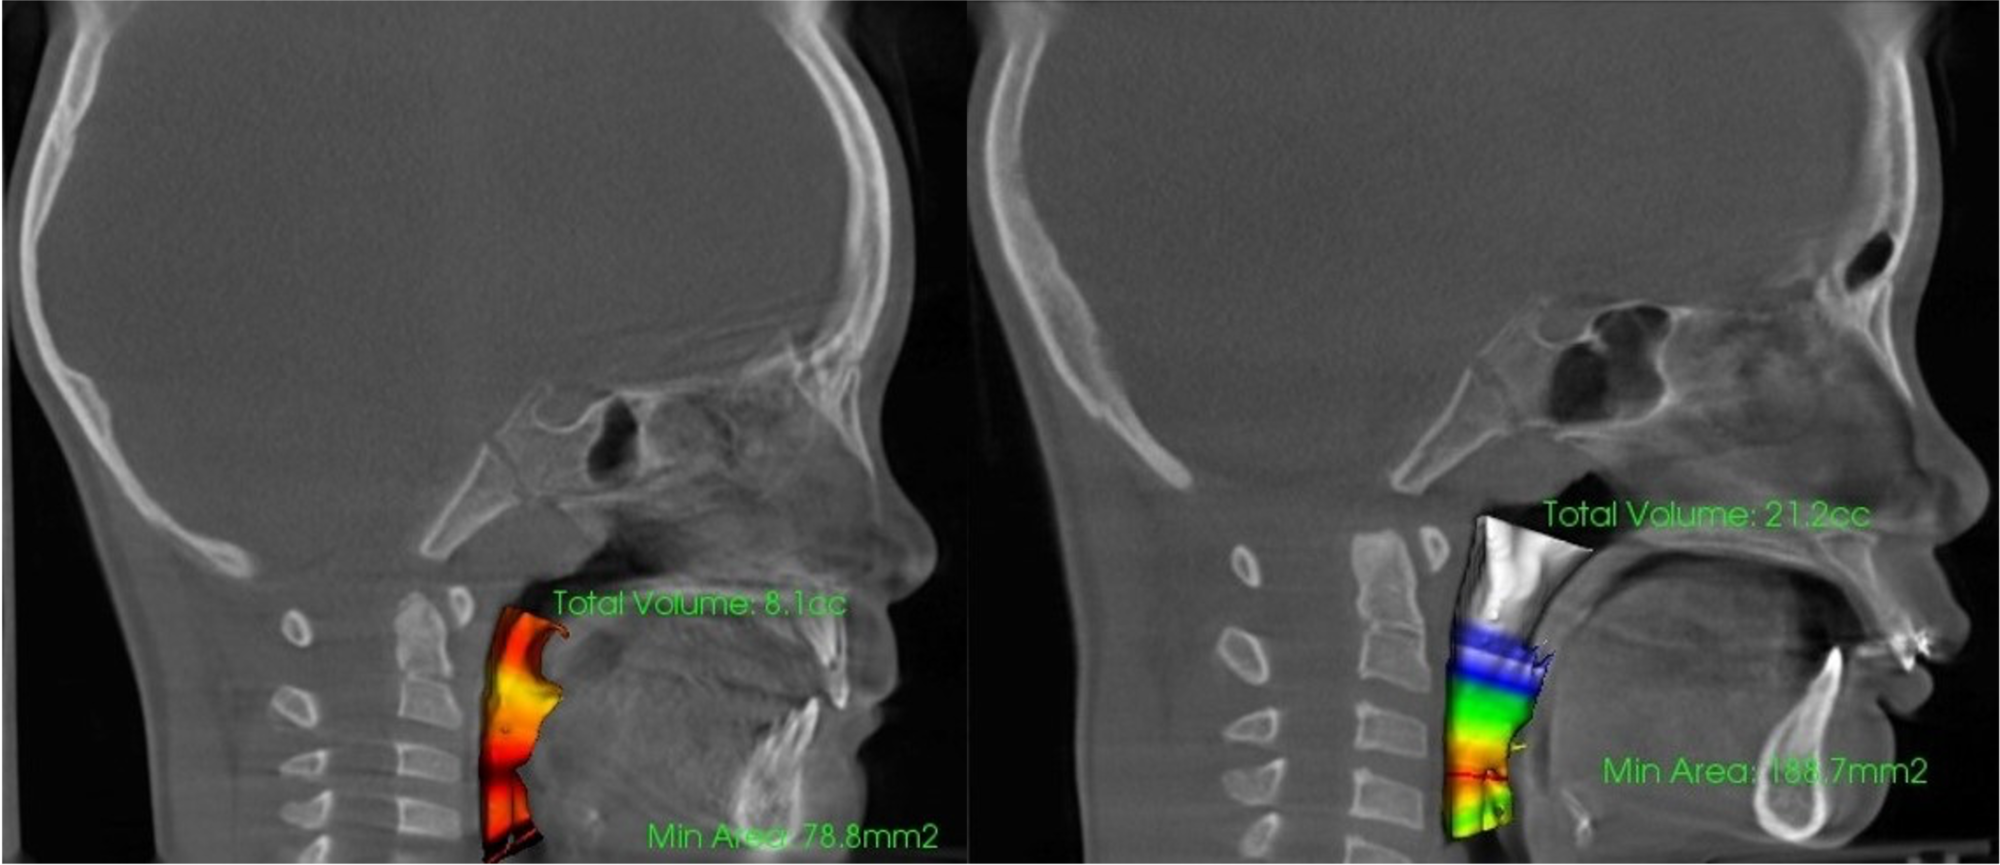

- 鼻副鼻腔容積・気道容積計測=呼吸時の通気性

気道容積

鼻腔容積

歯列

- 診断根拠:CT等による鼻腔・気道・骨格等の画像及び数値解析

- 評価指標:気道容積・鼻腔容積の数値変化、骨格変化の数値解析、舌骨の位置や姿勢の改善評価等